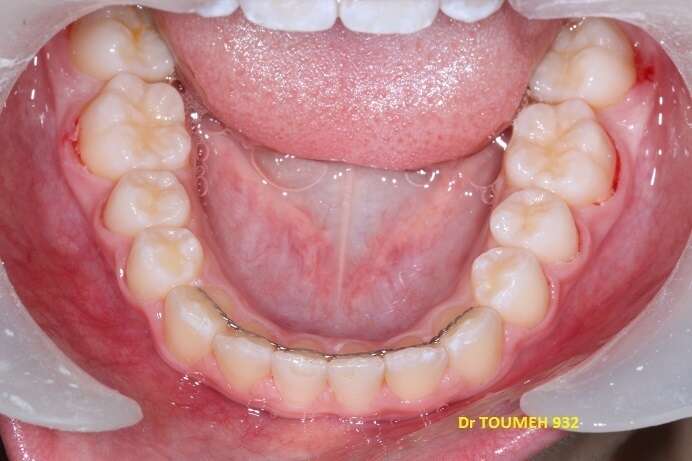

Avant

Après